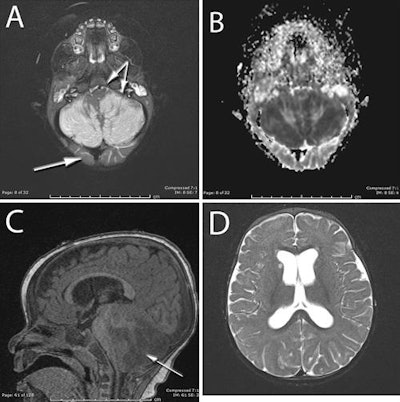

An MRI scan then showed severe swelling in the cerebellar hemispheres, which blocked the normal flow of cerebrospinal fluid. The MR images showed no damage to the upper part of the baby's brain.

MR images show severe swelling in the cerebellar hemispheres in a 10-month-old baby who accidentally ingested the drug ketamine. Images courtesy of the Journal of Neurosurgery: Pediatrics.The researchers noted that the MRI results were unusual because in most cases, the upper part of a person's brain is damaged from a lack of oxygen and the cerebellum is spared. This reversal of common findings suggested a specific association with ketamine.

Given this information, clinicians inserted a drain in the baby's brain to divert the spinal fluid, and they used surgical decompression to make room for the swelling and to reduce the pressure on the brain.

Six months after the incident and despite MR images showing permanent damage to the cerebellum, the child has achieved anticipated developmental milestones and normal muscle coordination, but with a slight delay in speech progression.